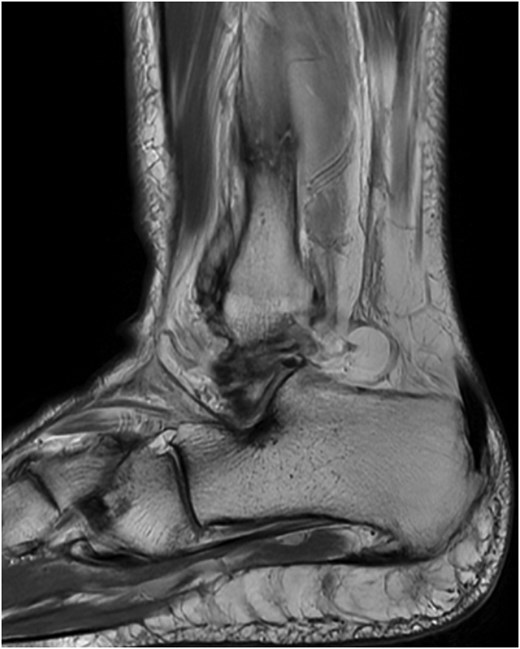

The patient is a 61-year-old female with a past medical history of idiopathic neuropathy with balance disorder, morbid obesity, and vitamin D deficiency presented to the clinic after she sustained an atraumatic injury to the right ankle. Notably, the patient required surgical treatment 2 years prior for an atraumatic left Weber C lateral malleolus fracture with Stage 3 posterior tibialis tendonitis and pes planus deformity (Fig. 1). Radiographs obtained at the time of injury to her right ankle showed no acute osseous abnormalities or dislocations and she was given a tall controlled ankle motion (CAM) boot. Magnetic resonance imaging (MRI) was later obtained demonstrating an acute Weber C fibular fracture with partial-thickness tearing of the syndesmotic membrane (Fig. 2). She was diagnosed with a right ankle lateral malleolus Weber C stress fracture. Patient initially elected for nonsurgical treatment but after a week with stable pain with limited function, she elected for surgical intervention a week after injury.

MRI demonstrating acute Weber C fibular fracture with partial-thickness tearing of the syndesmotic membrane of the right lower extremity.